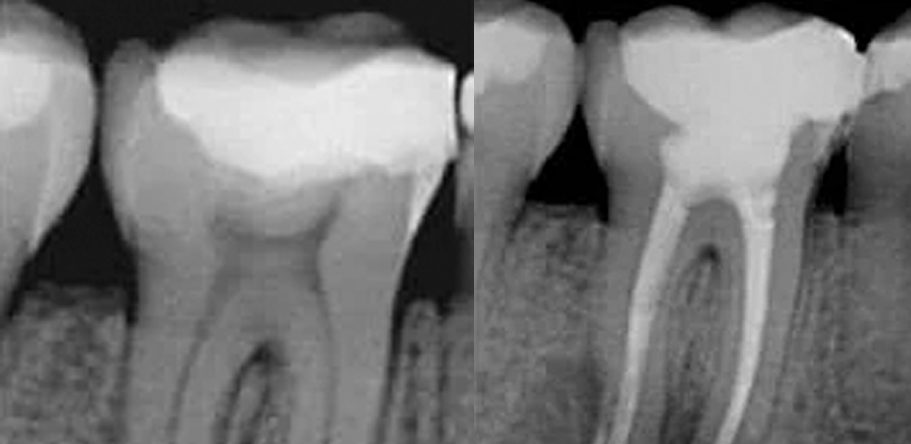

It’s a dental procedure designed to treat infections or damage inside a tooth. It involves removing the dental pulp (the soft tissue inside the tooth that contains nerves and blood vessels), followed by cleaning, disinfecting, and sealing the root canals. This treatment is recommended when the cavity is close to the nerve and is necessary when the pulp gets damaged or infected due to deep cavities. Its goal is to save the tooth and prevent it from being extracted.